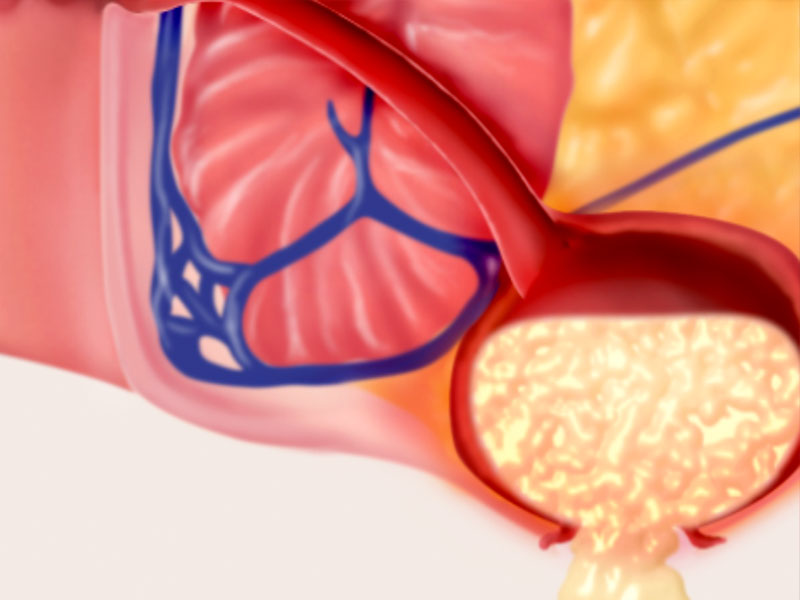

Anal Fistula

A fistula is a tract, a tunnel that begins inside the anal canal and burrows through surrounding tissues to the skin.